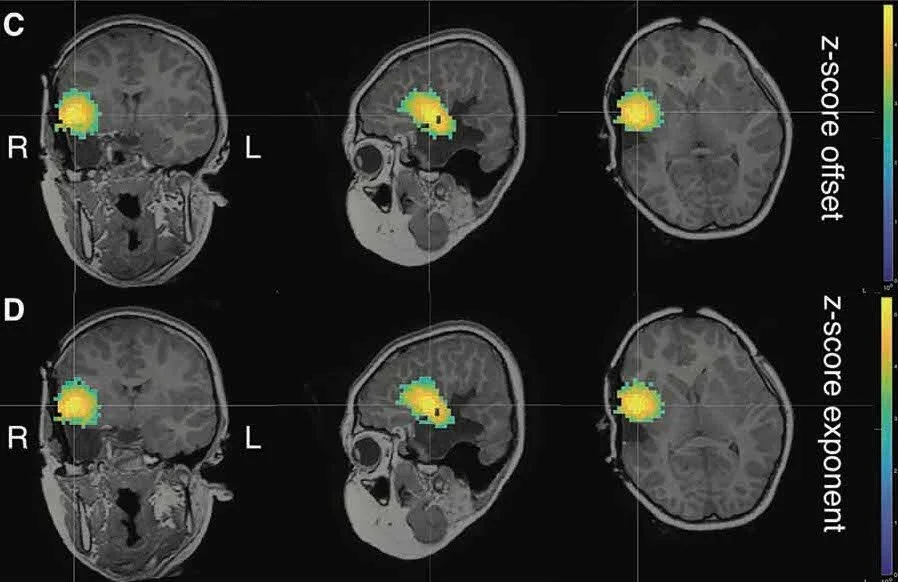

We investigated temporal changes & spatial differences (SOZ vs. control areas) in spectral parameters of background brain activity (aperiodic broadband offset & slope) & assessed how they confounded the interpretation of variations of signal power in typical frequency bands of electrophysiology.

Our data show that the SOZ was associated with a higher aperiodic offset & exponent during the seizure compared to control regions. Both parameters increased in all regions from 2 min before the seizure onwards.

Regions anatomically closer to the SOZ also expressed higher values compared to contralateral regions, potentially indicating ictal spread. We also show that narrow-band power changes were caused by these fluctuations in the aperiodic component of ongoing brain activity.

Our results indicate that the broadband aperiodic component of ongoing brain activity cannot be reduced to background noise of no physiological interest, and rather may be indicative of the neuropathophysiology of the SOZ.